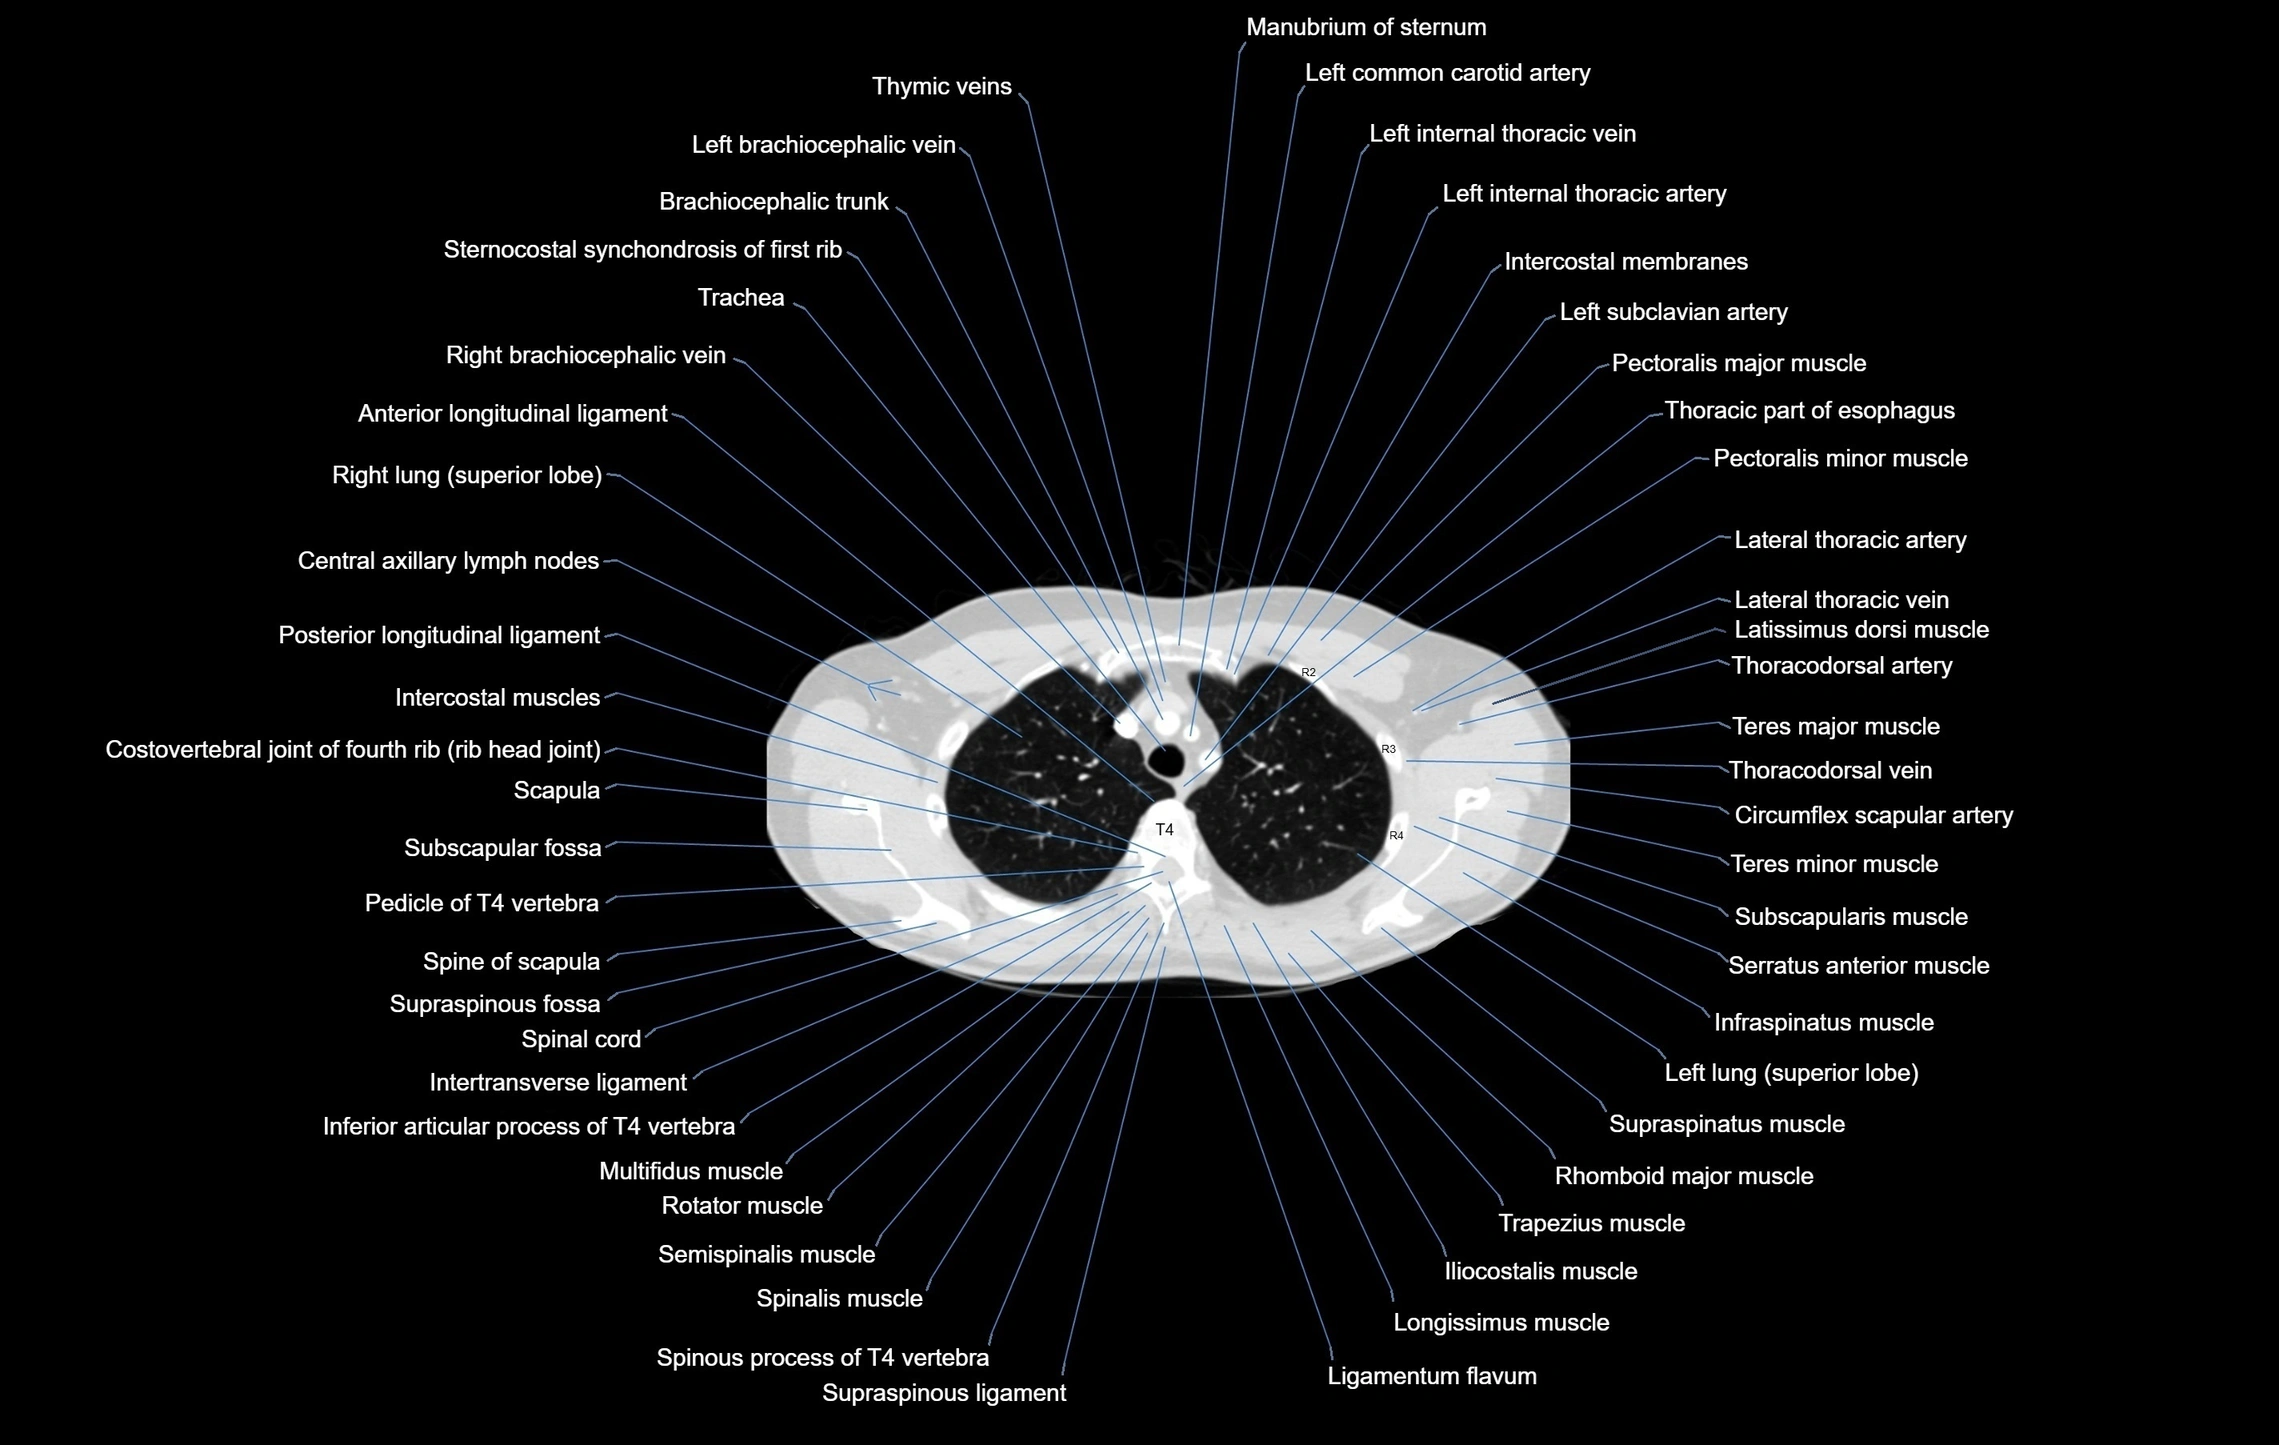

CT images